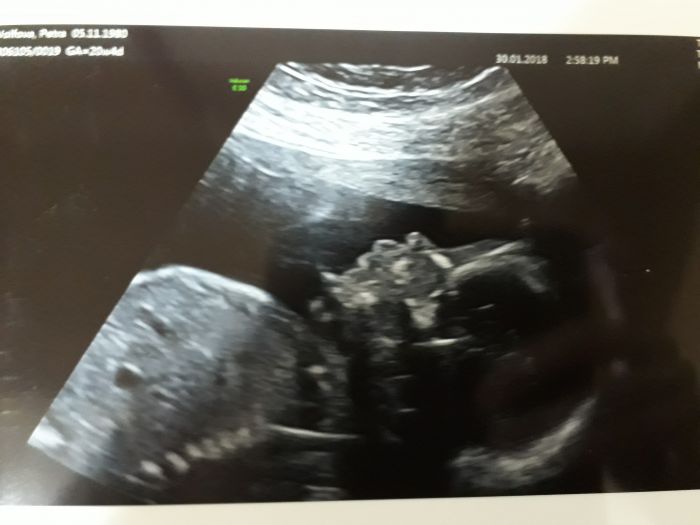

A omlouvám se, ale nedá mi to a musím se Martinkou pochlubit :-)

Nadherna fotecka! Moc a moc gratuluji :) nas to take ceka pristi tyden tak uz se moc tesime. Ale my uz vime, ze budeme mit chlapecka :) uz nam to potvrdilo dva doktori, takze ma vybavicka uz zari modrou barvickou